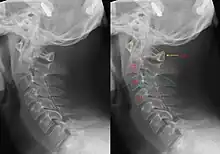

Hangman's fractureHangmanfracture of both pedicles of C2distraction and extension of neckHangman's fracture Archived 2020-09-18 at the Wayback Machine at Wheeless' Textbook of Orthopaedics online

Clay shoveller's fractureClay shovellersspinous process fracture of C6, C7 or T1forced hyperflexion of neck"Clay shovellers fracture". Medcyclopaedia. GE. Archived from the original on 2011-05-26. Retrieved 2023-03-25.